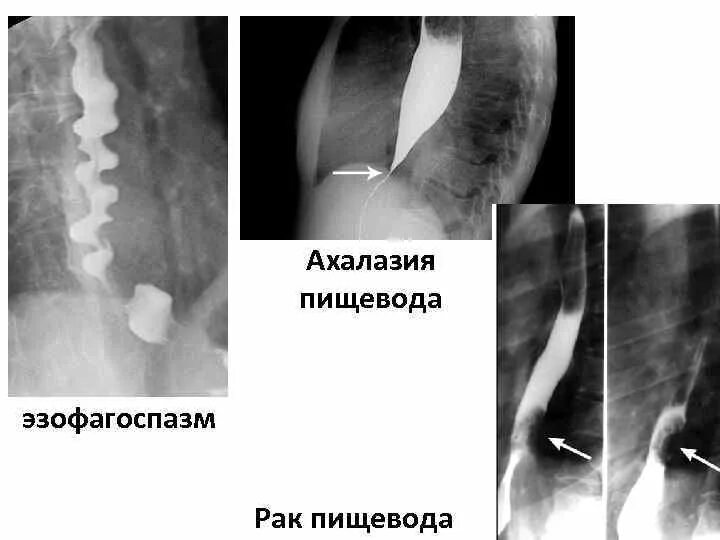

Диффузный эзофагоспазм